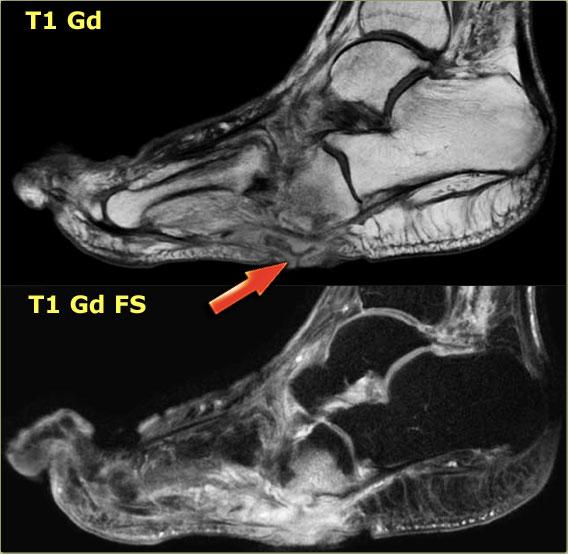

Đây là hình ảnh MRI của một bệnh nhân bị bệnh xương khớp thần kinh Charcot cấp tính.

Phù tủy xương thường không giới hạn ở một hoặc hai xương, mà xuất hiện ở toàn bộ bàn chân giữa.

Phù tủy xương và sự ngấm thuốc của nó thường tập trung ở vùng xương dưới sụn, gợi ý bệnh lý khớp.

Mô dưới da tương đối bình thường và không có vết loét hay các dấu hiệu nhiễm trùng khác.

Hình ảnh STIR và T1 bên trái của bệnh nhân bị bệnh xương khớp thần kinh Charcot đang hoạt động với vết loét lòng bàn chân dọc theo chỗ lồi xương của xương hộp.

Có tín hiệu bất thường trong xương hộp cạnh vết loét, gợi ý viêm tủy xương.

Đây là các hình ảnh tăng cường tương phản có và không có bão hòa mỡ.

Sự tăng cường của xương hộp và các mô mềm lân cận trên hình ảnh sau tiêm thuốc tương phản, cùng với vết loét lòng bàn chân, làm cho viêm tủy xương rất có khả năng xảy ra.